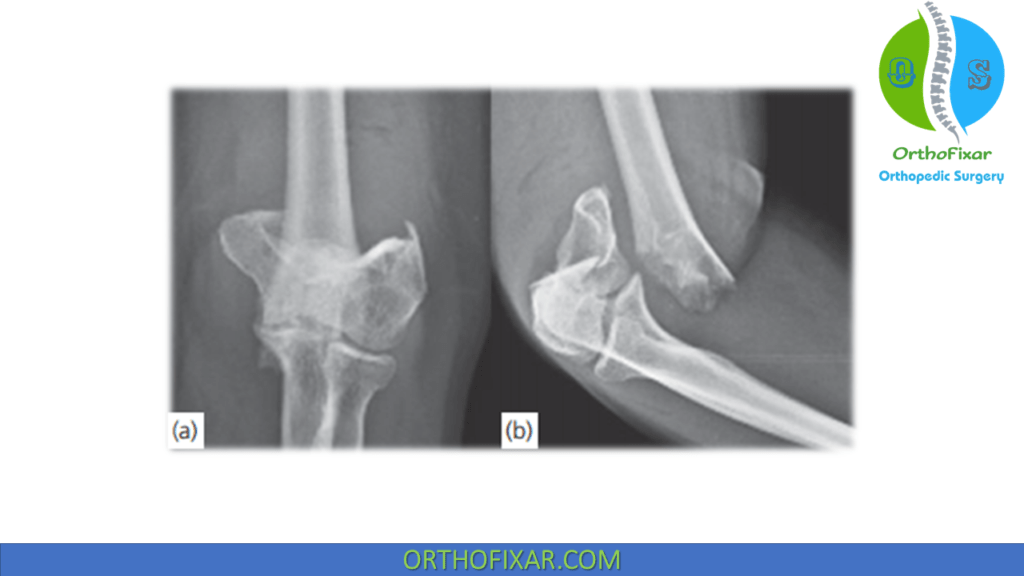

Type C33 right distal humerus fracture; preoperative xrays (A and B Distal Humerus Fracture X Ray Depending on your symptoms, your doctor may. A tiny bony density is seen projected anterior to the distal humerus, with linear lucencies projected. Magnetic resonance imaging (mri) : This can be in the form of a direct blow to the affected extremity by either foreign object or fall. Difficult injury to manage due to: Distal humerus fractures are traumatic injuries. Distal Humerus Fracture X Ray.

Distal Humerus Fracture OrthoFixar 2024 Distal Humerus Fracture X Ray This can be in the form of a direct blow to the affected extremity by either foreign object or fall. Magnetic resonance imaging (mri) : Distal humerus fractures are traumatic injuries to the elbow that comprise of supracondylar fractures, single column fractures, column fractures or coronal shear. A tiny bony density is seen projected anterior to the distal humerus, with. Distal Humerus Fracture X Ray.